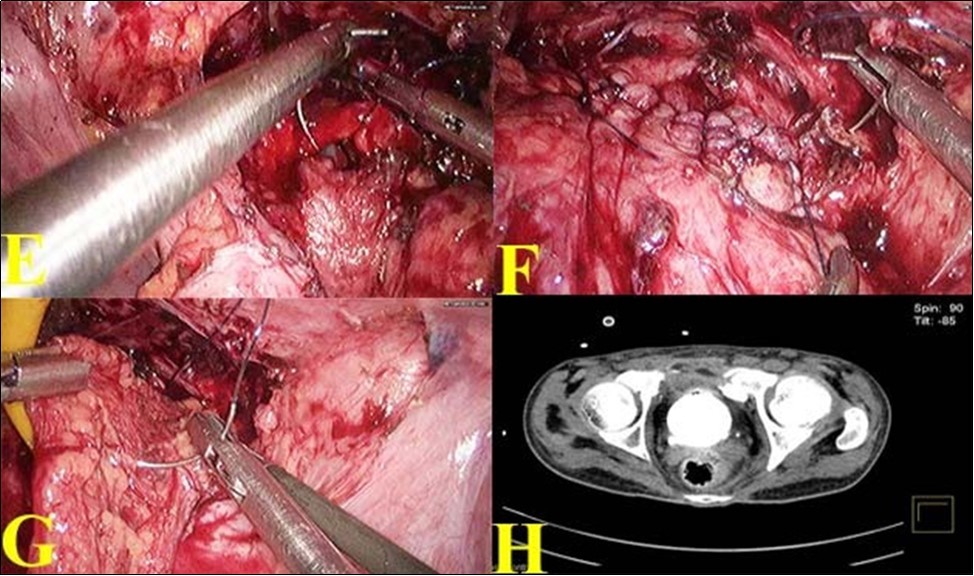

(Figure 2 (G). SPC was reinserted. Bladder was again distended with dilute methylene blue solution to make sure that the closure was watertight. A tube drain was placed. Postoperatively patient made an uneventful recovery. Tube drain was removed on 7thpostoperative day when the drainage was less than 10ml. SPC was removed on the 10thpostoperative day. CT cystogram was done on 21st day which showed no extravasation Figure 2 (H). Patient voided freely on removal of urethral catheter on 21st day.

Figure 2.E. Bladder rent closing with barbed suture ; F. Suturing completed; G. Omental reinforcement over the suture line; H. Post operative CT showing healed bladder.